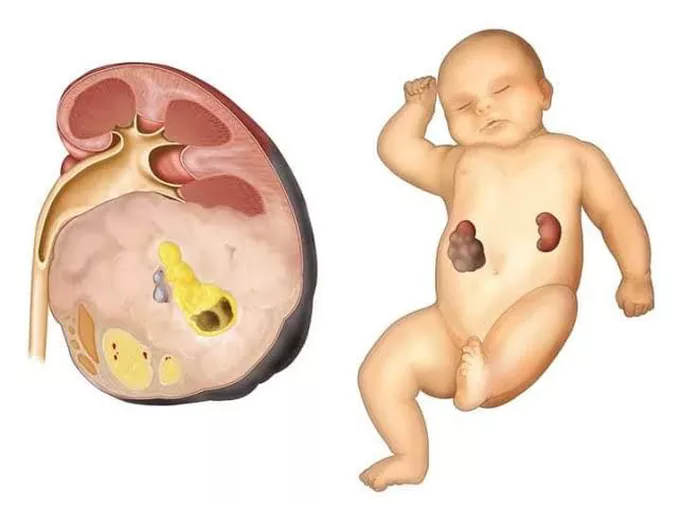

Wilms tumor is a rare form of kidney cancer that primarily affects children, most commonly under the age of five. It develops when immature kidney cells grow abnormally and form a tumor in one or both kidneys. Although the condition can sound alarming, advancements in pediatric oncology have made Wilms tumor one of the most treatable childhood cancers when detected early.

Diagnosing Wilms tumor involves a detailed medical assessment and specialized imaging tests. These investigations help doctors determine the size, location, and stage of the tumor.

Wilms tumor is a rare type of kidney cancer that mainly affects young children, usually under the age of five. It develops when kidney cells grow abnormally and form a tumor.

Can Wilms tumor affect both kidneys?

In most cases it affects only one kidney, but in rare cases both kidneys may be involved.